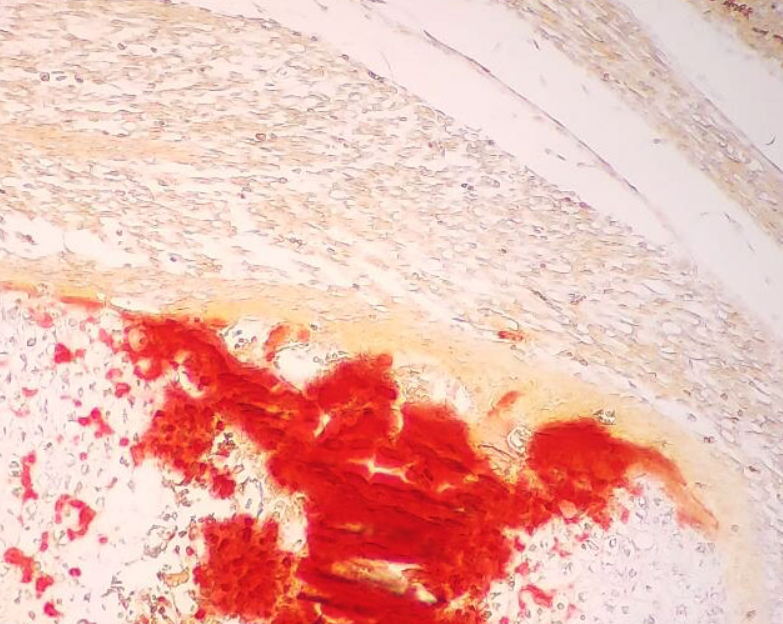

4、天狼猩红染色实验结果(大鼠肝脏举例)

天狼猩红实验结果解读:普通光学显微镜下,胶原纤维呈现红色或者橙红色;复染苏木精,细胞核呈现蓝色或者紫蓝色。偏振光显微镜下,Ⅰ型胶原成像橙黄色或者亮红色,Ⅲ型胶原呈现亮绿色。